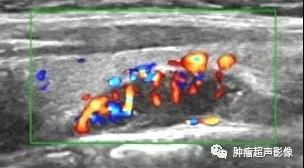

病理证实的甲状旁腺腺瘤:位于甲状腺下极旁,完整的包膜,呈低回声,血流丰富且为典型的极性血供,由一端进入后呈分支分布,符合典型的甲状旁腺腺瘤。